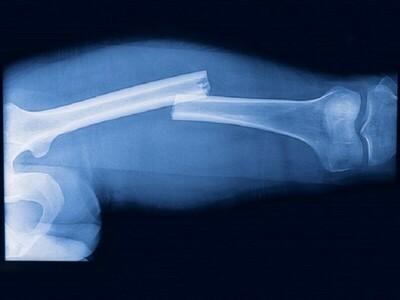

Перелом костей – это состояние, которое характеризуется частичным или полным повреждением анатомической целостности кости, что в свою очередь приводит к нарушению тканей, находящихся вокруг кости. При этом происходит нарушение функций кости, которая была поражена.

- рентгенологическое исследование;